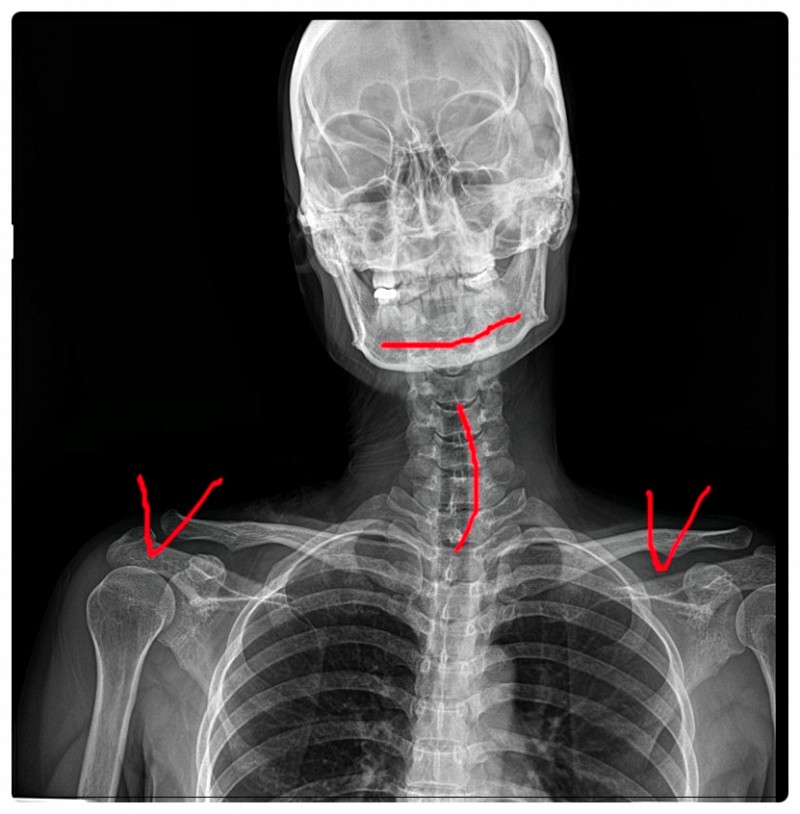

Q. 어깨가 아픈데 시작은 목일 수 있습니다.

어깨 근육 통증을 살펴볼 때

제가 가장 먼저 확인하는 곳이 바로 목입니다.

어깨로 내려가는 대부분의 신경이 목, 특히 경추에서 시작되기 때문인데요.

경추의 정렬이 무너져 있거나 미세하게 불균형이 지속되는 분들이 있습니다.

이런 경우, 신경이 지나가는 공간이 좁아지면서

어깨 주변에 통증이나 저림이 나타날 수 있습니다.

이때 어깨만 집중적으로 관리하면 회복이 더딜 수 있습니다.

그래서 경추 상태를 확인하고 필요하다면 교정을 통해

신경이 압박받지 않도록 공간을 확보하는 과정이 중요합니다.

이것이 단순히 어깨만 바라보고 치료하지 않았던 이유입니다.